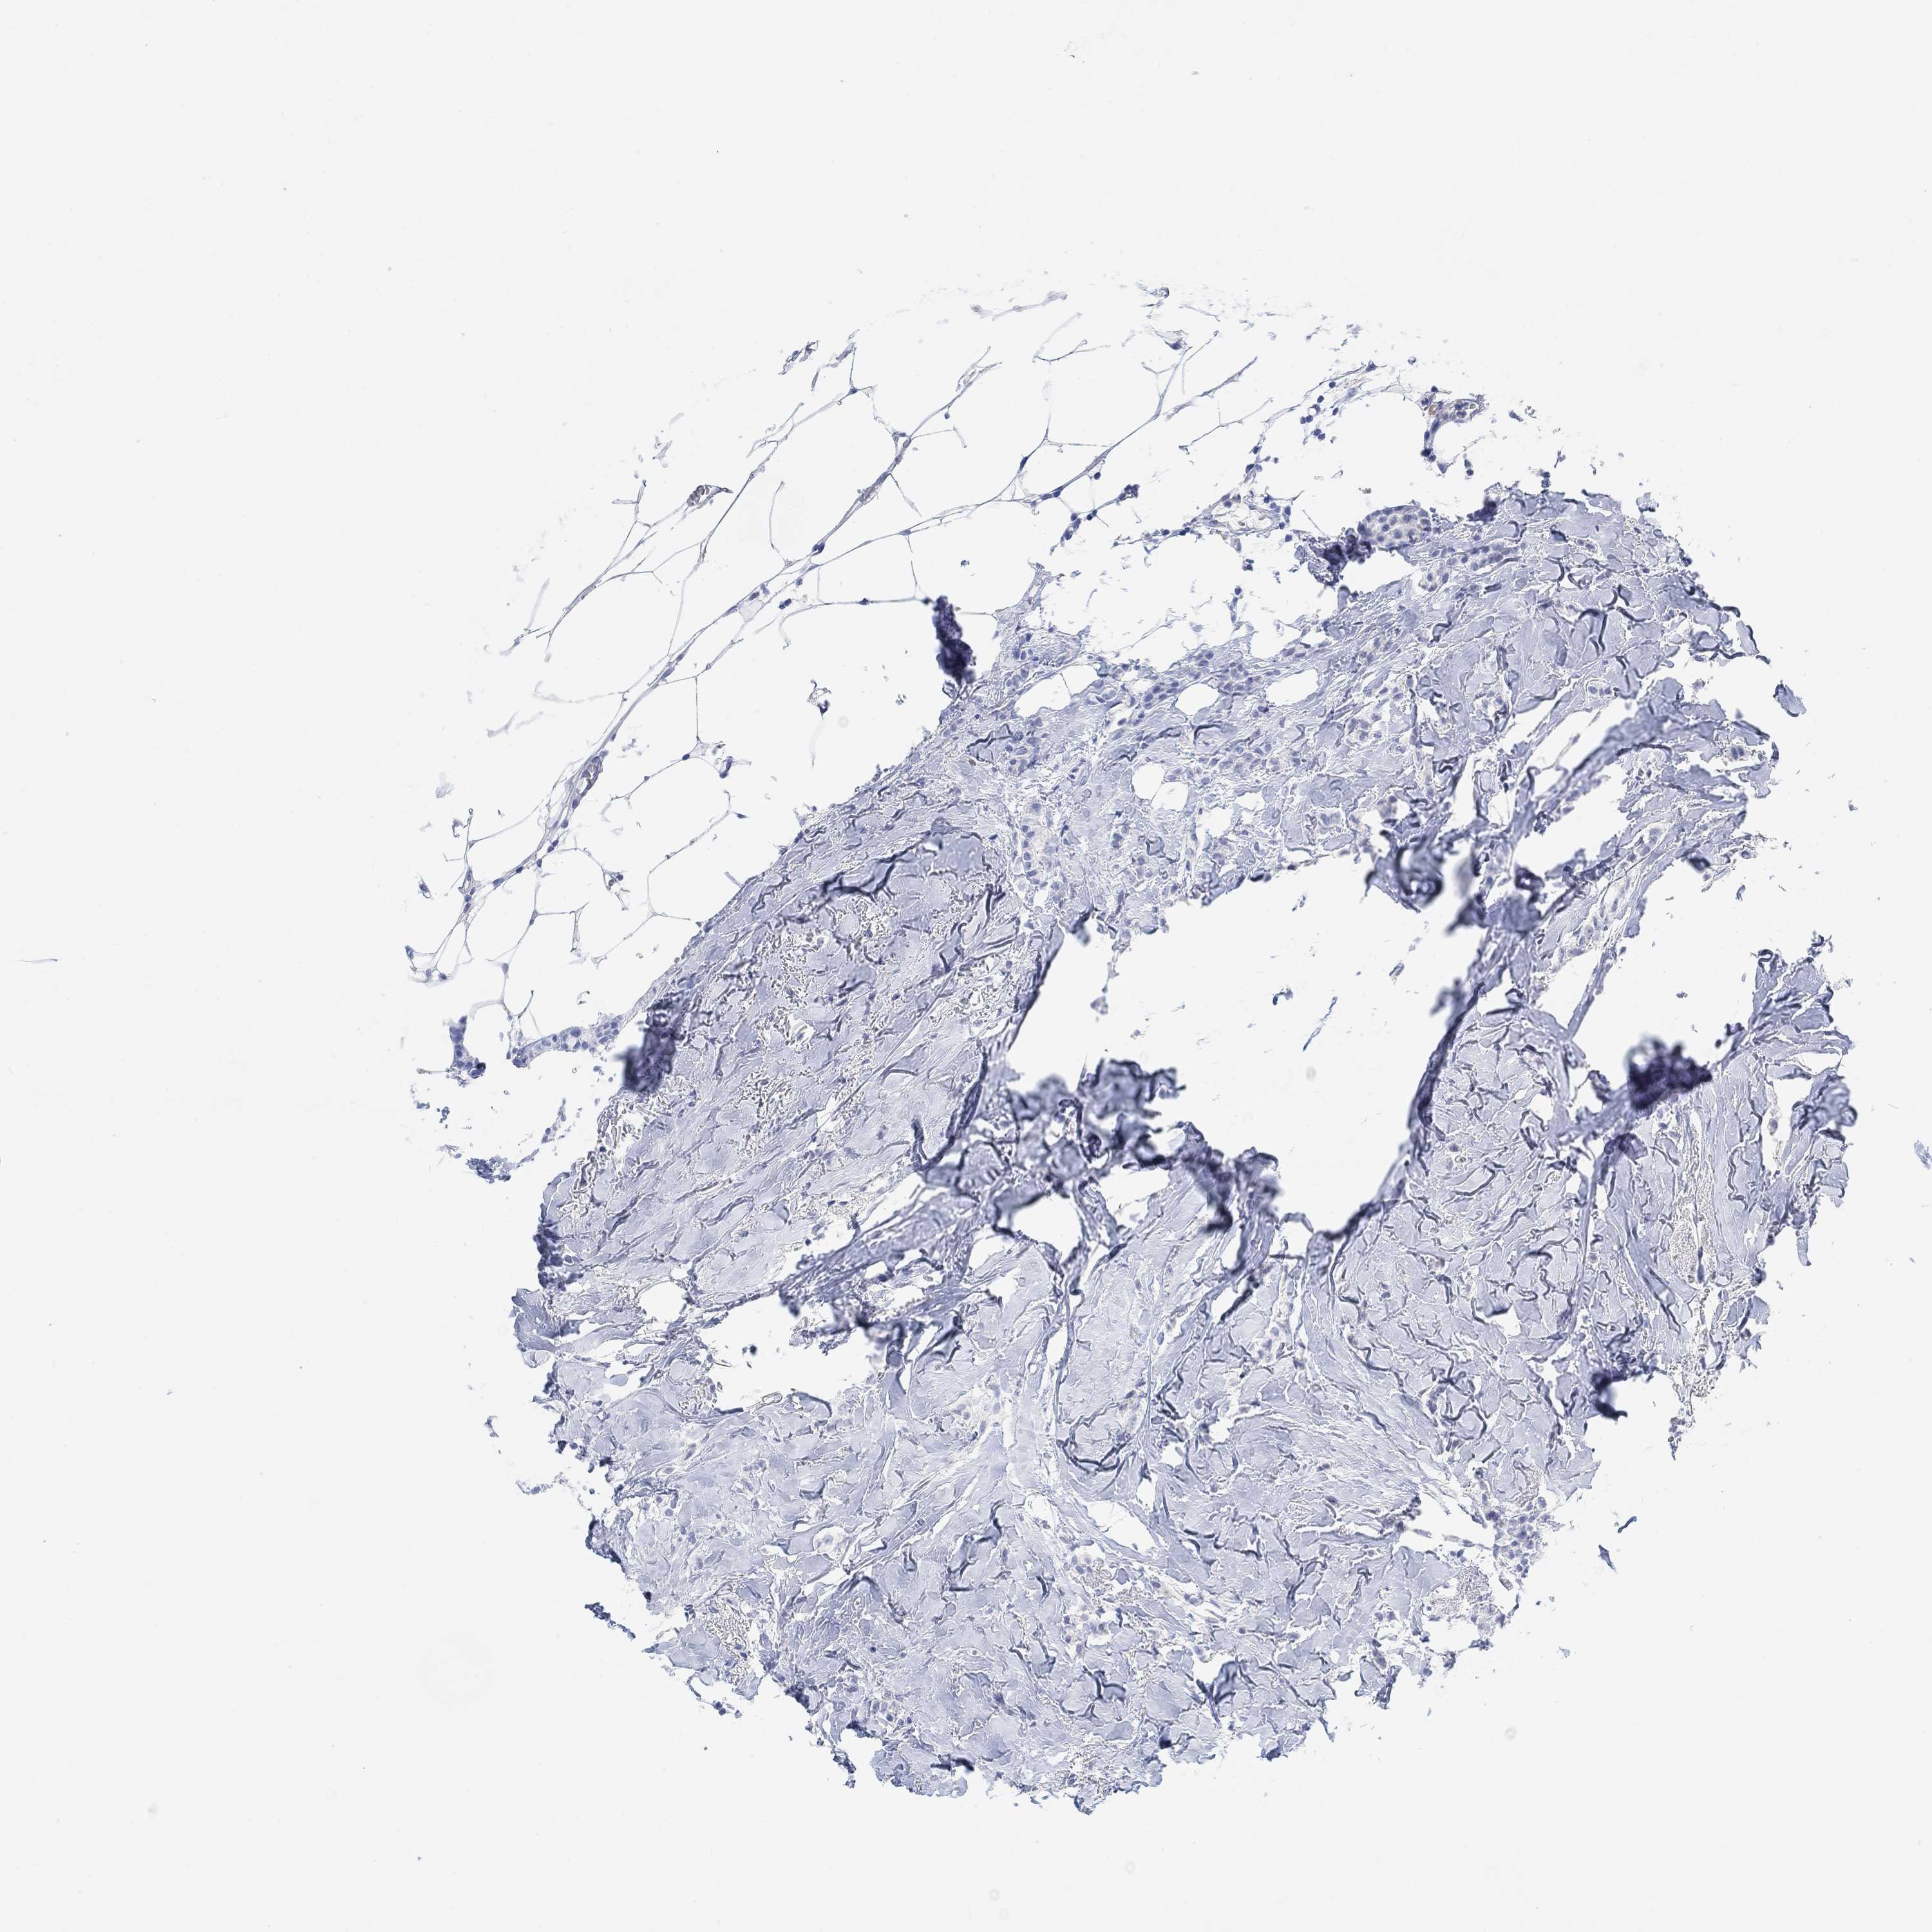

BRCA TCGA BRCA VALIDATION PROTEIN EXPRESSION

ANTIBODIES

AND

VALIDATION